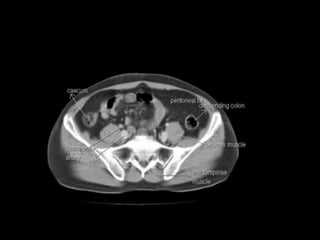

PERITONEUM ANATOMY

Peritoneum

Mesenteries

True mesenteries all connect to the

posterior peritoneal wall.

These are:

The small bowel mesentery

The transverse mesocolon

The sigmoid mesentery (or

mesosigmoid)

Specialized mesenteries do not

connect to the posterior peritoneal

wall.

The greater omentum: connects the

stomach to the colon

The lesser omentum: connects the

stomach to the liver

The mesoappendix: connects the

appendix to the ileum